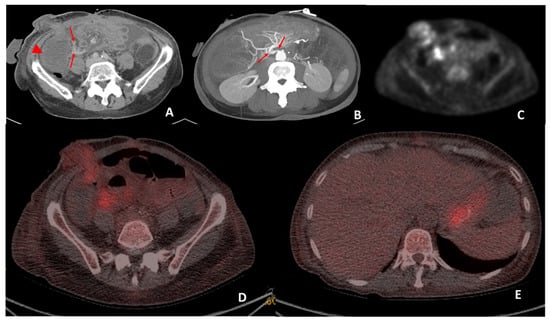

Figure 5. CT performed on day 19 post transplant for sepsis and query ischemia or rejection. Portal venous-phase CT imaging was performed on day 19 post transplant (A) demonstrating subtle mural oedema in the caecum (arrowhead) and sub centimeter mesenteric lymph nodes (arrows) surrounding the caecum. Maximum intensity projection (B) of the superior mesenteric origin on post-operative day 19 CT demonstrates a double kink (arrows) at this site. The patient subsequently underwent angiography and pressure measurements, which demonstrated a 27 mmHg pressure gradient between the aorta and SMA. Angioplasty was performed and reduced the pressure gradient to 21 mmHg. Attenuation-corrected 18F-FDG PET (C) demonstrated increased uptake in the mucosa of the small bowel surrounding the stoma and the mesenteric lymph nodes. Hybrid imaging 18F-FDG PET-CT demonstrated co-localisation of the increased uptake to the small bowel surrounding the stoma and also at the mesenteric lymph nodes (D). Biopsies performed on the small bowel surrounding the stoma were reported to be in keeping with mild rejection. The increased low-grade uptake in the stomach (E) was interpreted as physiological uptake.